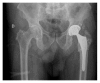

More than twenty years ago, hydroxyapatite (HA), calcium phosphate ceramics, was introduced as a coating for cementless hip prostheses. The choice of this ceramic is due to its composition being similar to organic apatite bone crystals. This ceramic is biocompatible, bioactive, and osteoconductive. These qualities facilitate the primary stability and osseointegration of implants. Our surgical experience includes the implantation of more than 4,000 cementless hydroxyapatite coated hip prostheses since 1990. The models implanted are coated with HA in the acetabulum and in the metaphyseal area of the stem. The results corresponding to survival and stability of implants were very satisfactory in the long-term. From our experience, HA-coated hip implants are a reliable alternative which can achieve long term survival, provided that certain requirements are met: good design selection, sound choice of bearing surfaces based on patient life expectancy, meticulous surgical technique, and indications based on adequate bone quality.